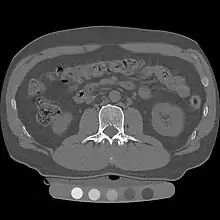

Quantitative computed tomography (QCT) is a medical technique that measures bone mineral density (BMD) using a standard X-ray computed tomography (CT) scanner with a calibration standard to convert Hounsfield units (HU) of the CT image to bone mineral density values.[1] Quantitative CT scans are primarily used to evaluate bone mineral density at the lumbar spine and hip.

Originally, conventional 2D QCT used individual, thick CT slice images through each of multiple vertebrae which involved tilting the CT scanner gantry to align the slice with each vertebra. Today, modern 3D QCT uses the ability of CT scanners to rapidly acquire multiple slices to construct three-dimensional images of the human body. Using 3D imaging substantially reduced image acquisition time, improved reproducibility and enabled QCT bone density analysis of the hip.[1]

Dual use of CT images

Several studies have shown that bone density may be measured by QCT using CT images that were ordered for other purposes. Using pre-existing images, including CT colonography exams,[14] QCT allows for bone density screening without submitting the patient to any additional radiation exposure. The feasibility of using routine abdominal contrast-enhanced CT scans for the evaluation of bone density by QCT has also been demonstrated.[15]